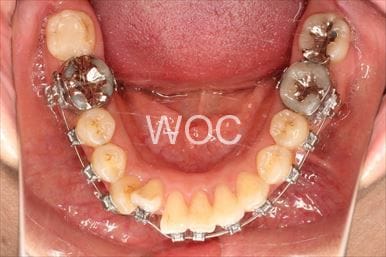

八重歯・叢生舌側矯正

上下舌側矯正を希望。奥歯を後方へ移動し、非抜歯で治療を終わることができました。

- 年齢:17歳女性

- 主訴:前歯が斜めになっている

- 基本矯正料金:1,250,000円

- 治療期間:1年7ヶ月

- 非抜歯